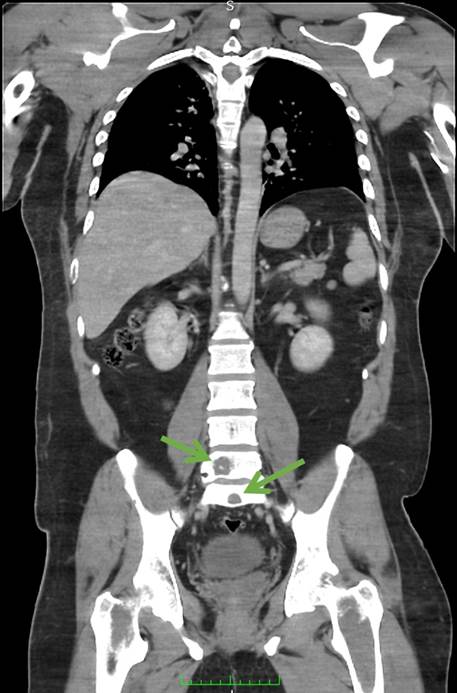

Durante el seguimiento presenta deterioro del estado funcional progresivo, recibiendo manejo por medicina paliativa y oncología médica. A los dos meses con síndrome medular incompleto, caracterizado por disminución de la fuerza en extremidades inferiores con imposibilidad para la deambulación y dolor. Se evidencian sitios de metástasis a columna toracolumbar mediante estudio tomográfico de control (Figura 3), continuando manejo a base de esteroides y opiáceos. El paciente falleció al tercer mes de diagnóstico, sin llegar a recibir manejo con radioterapia ni quimioterapia.